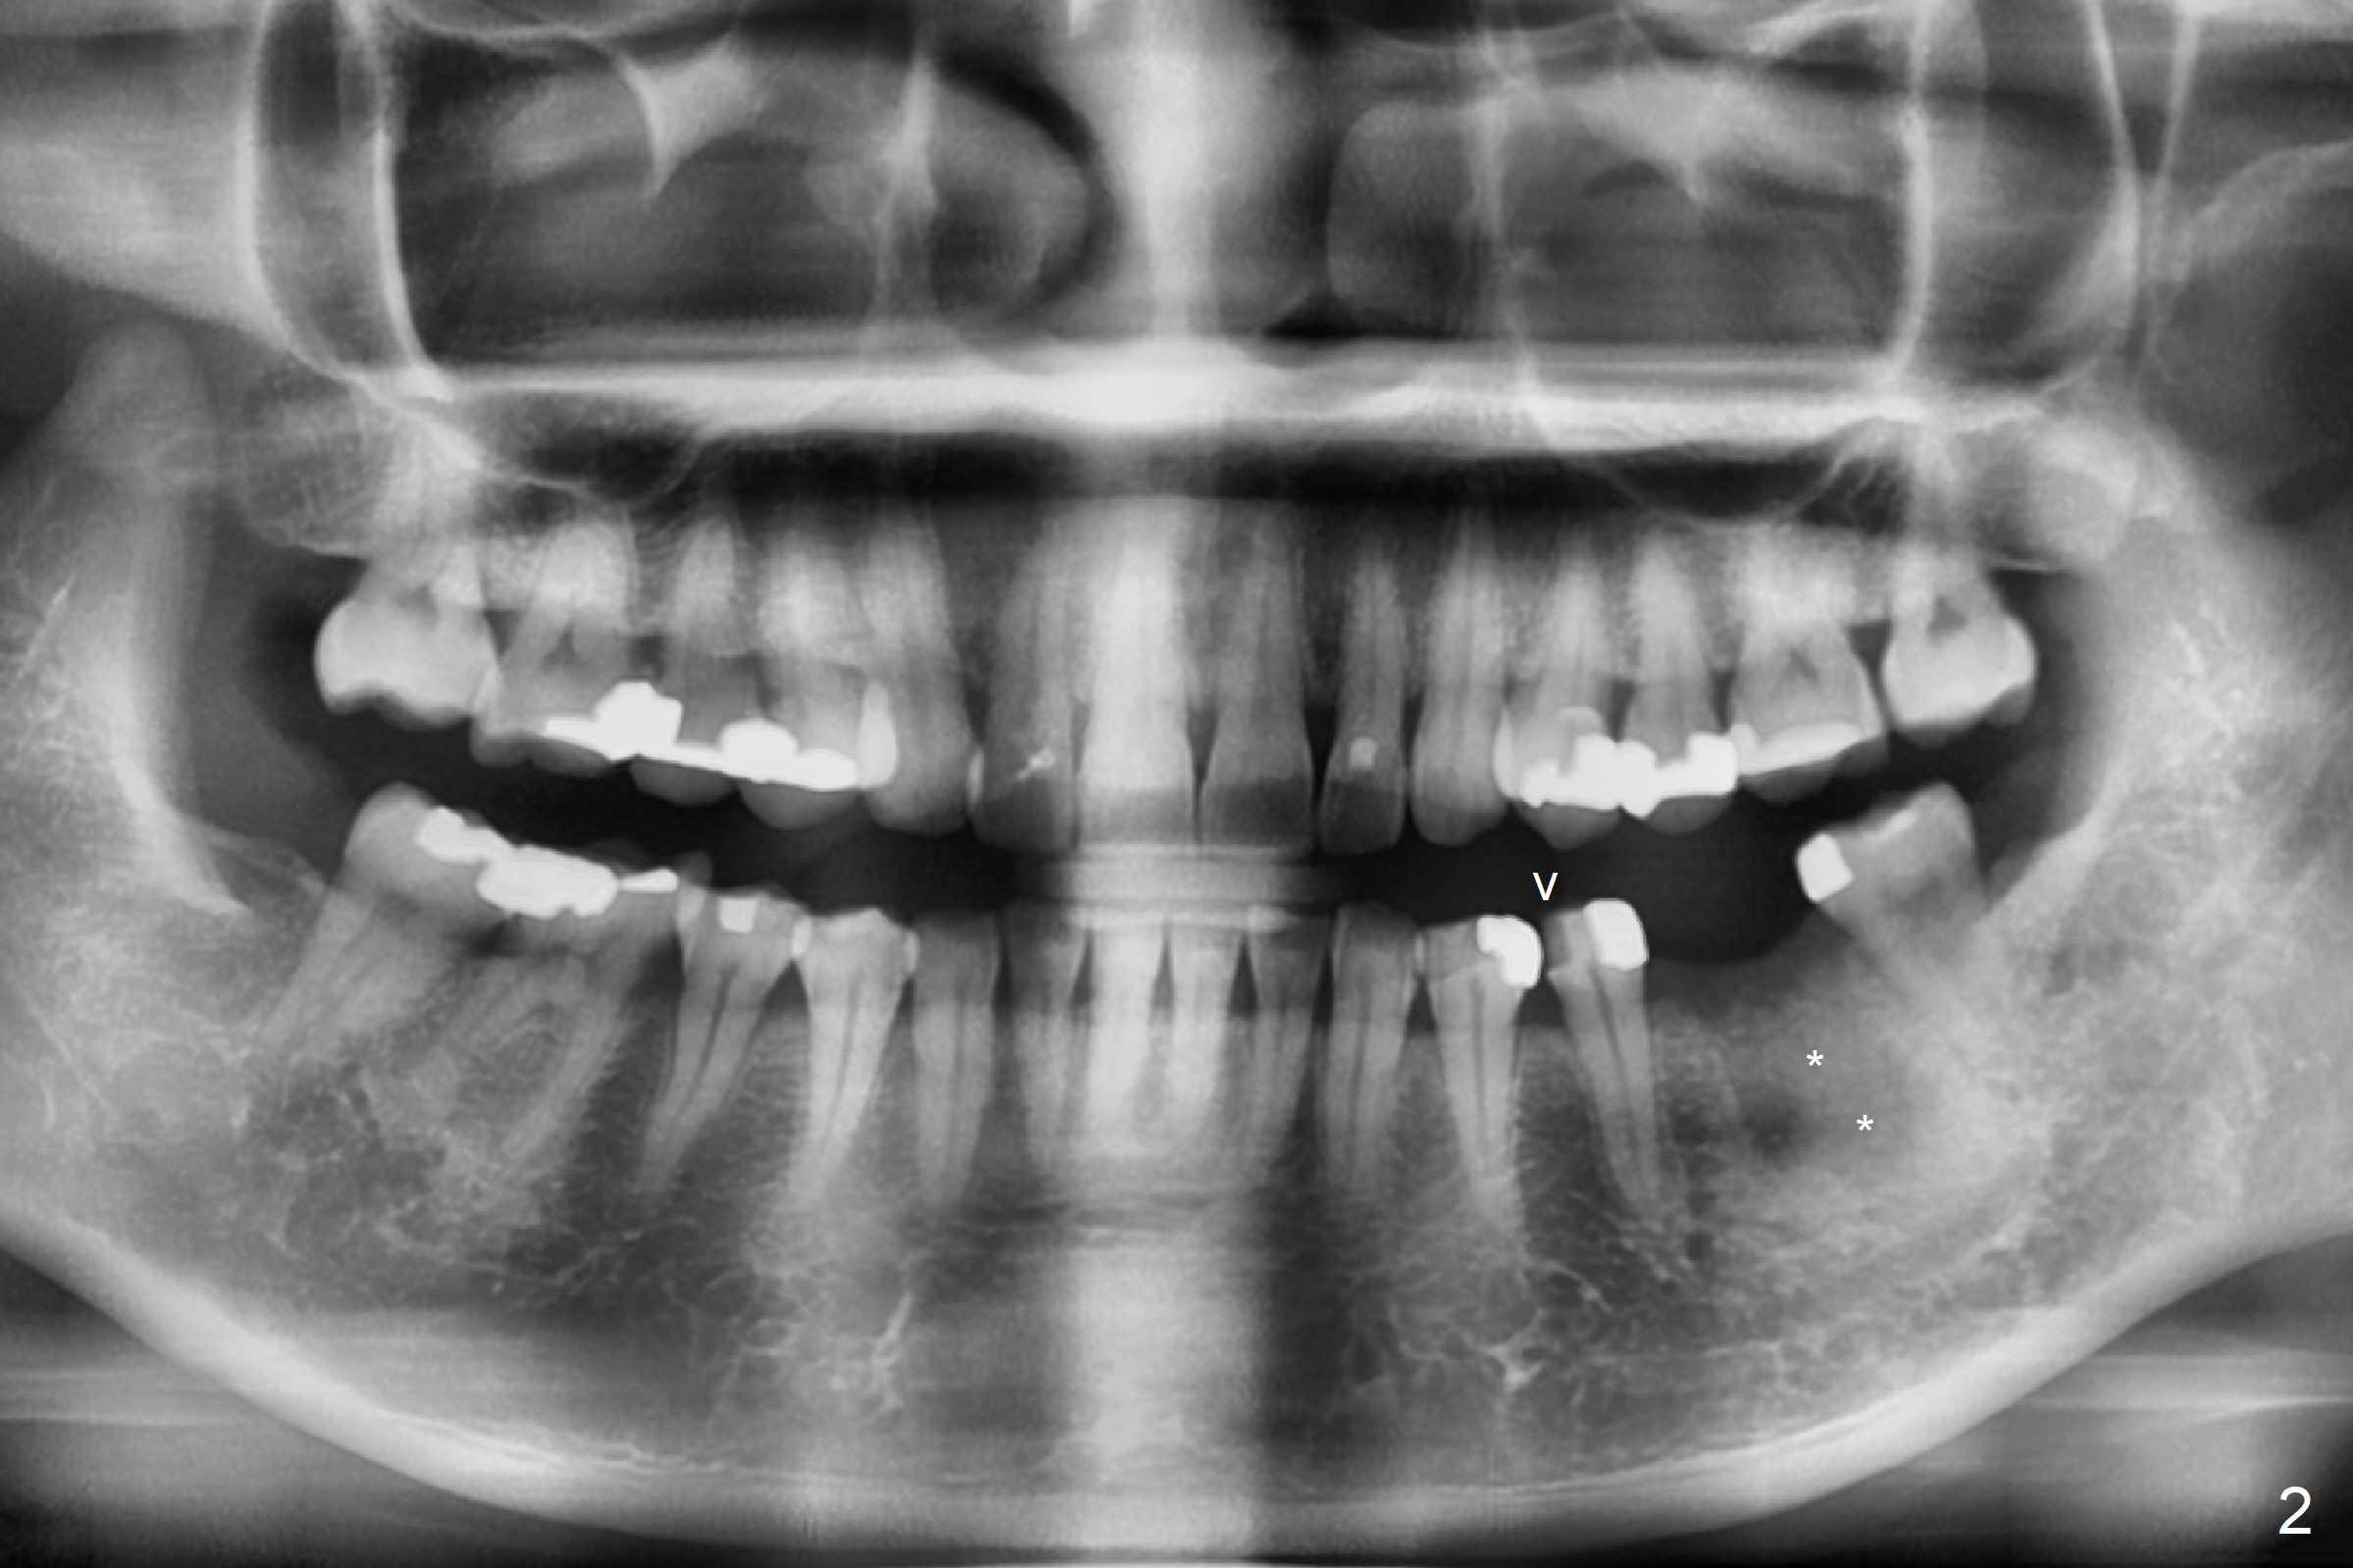

A 53-year-old woman has discomfort at #19 4-5 years post RCT (Fig.1 (*: PARL), 1 year before extraction). She returns for implant placement 4 months post socket preservation in other office (Fig.2 *). The socket appears to have healed with dense bone formation (average 1160 units, Fig.3). A 5x11.5 mm implant will be placed with guide (Fig.4). Will composite at #20 MOL (Fig.2 arrowhead) and PVS impression after CBCT affect surgical guide fabrication accuracy? Or the composite should be done after guided surgery?